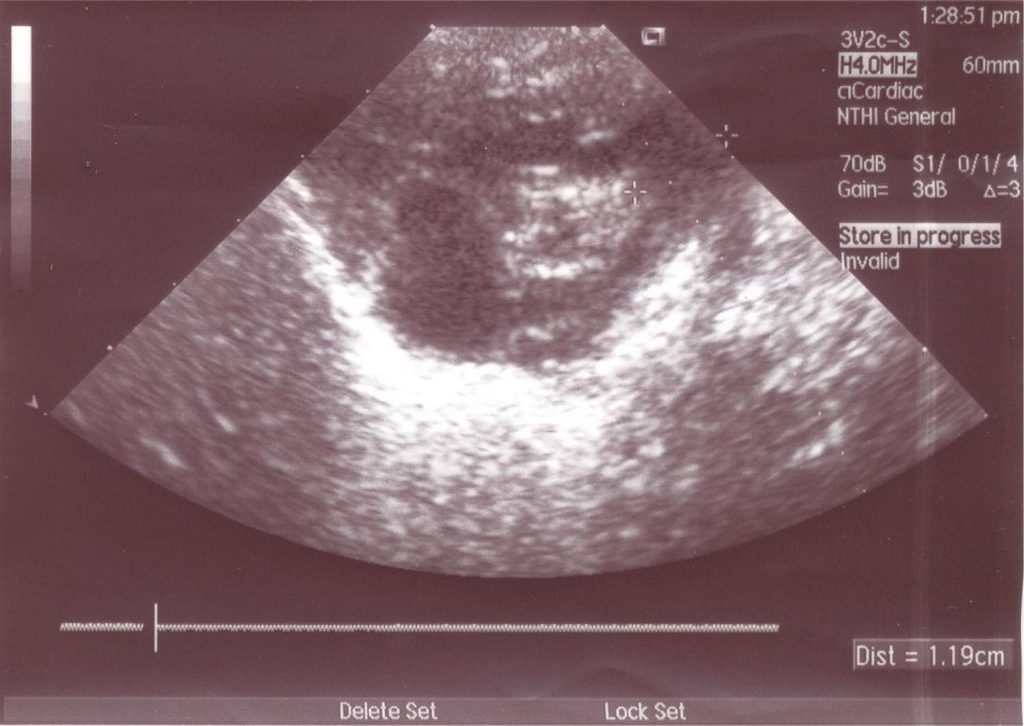

Figure 3

Ostium Secundum atrial septal defect and increase of AD and pulmonary artery trunk dilated.